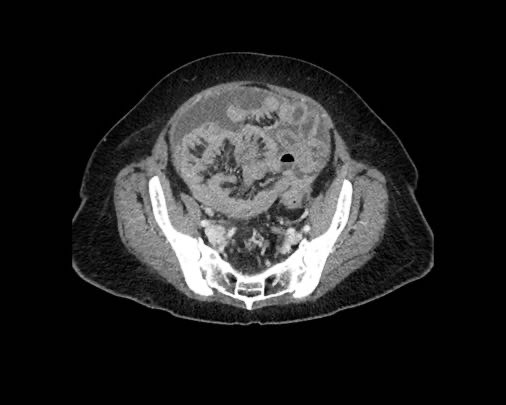

Ca lâm sàng 2

Cuộn qua các lát cắt.

Bạn có thể phát hiện tất cả các tổn thương cấy ghép phúc mạc không?

.jpeg)